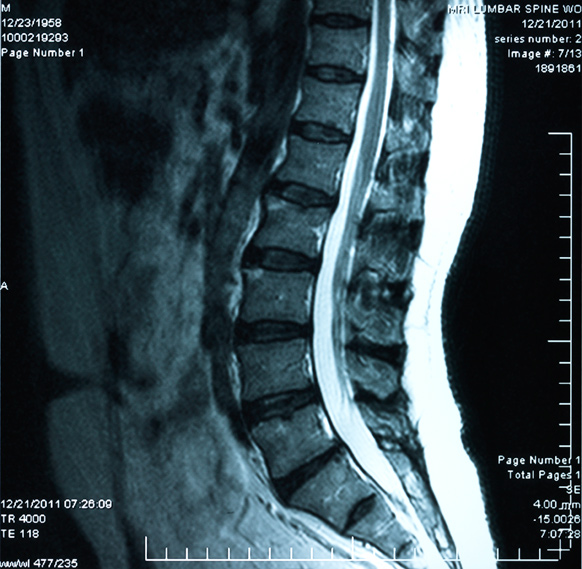

Отделы позвоночника для мрт схема фото и названия